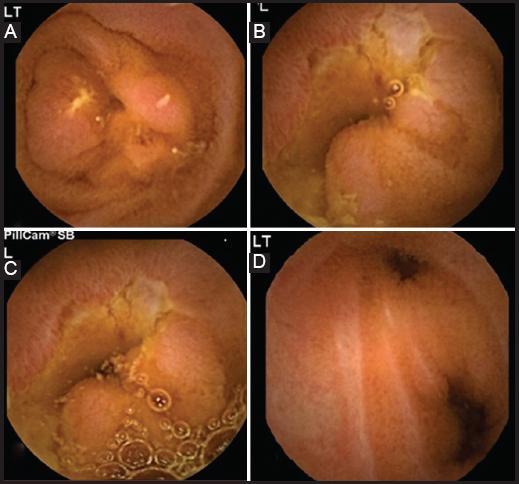

Se realizó laparotomía exploradora y se identificó distensión generalizada de asas de intestino delgado en íleon con zonas de diminución del diámetro intestinal y datos macroscópicos indicativos de inflamación aguda y crónica (Fig. 2). En el íleon, a 110 cm de la válvula ileocecal, se reconoció un área de estenosis concéntrica y se palpó la CE impactada (Fig. 3). Se efectuó resección de 60 cm del segmento afectado y luego se creó anastomosis intestinal laterolateral con engrapadora mecánica tipo GIA de 75 mm. Se constataron la permeabilidad y la ausencia de fuga de la anastomosis. El estudio histopatológico informó lo siguiente: pieza quirúrgica de íleon con disminución de la luz secundaria a proceso fibroestenótico, con obstrucción de la luz por cápsula endoscópica impactada en la zona de estenosis de unos 6 cm y signos de enfermedad de Crohn activa. El informe de la cápsula endoscópica reveló úlceras y divertículos en yeyuno y datos de retención con falla de paso al colon (Fig. 4).